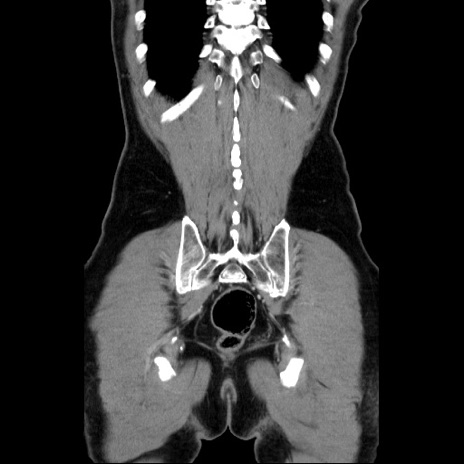

症例34(冠状断像)

【症例】60歳代 男性

【主訴】右鼠径部膨隆

【現病歴】1年程前より右鼠径部膨隆あり。自己にて還納可能だったため放置していた。3時間前より右鼠径部の脱出を認め、還納困難となり受診。

【身体所見】右鼠径部に小児頭大の膨隆あり。弾性硬であり、用手還納は困難。左鼠径部にも膨隆を認める。脱出はなし。